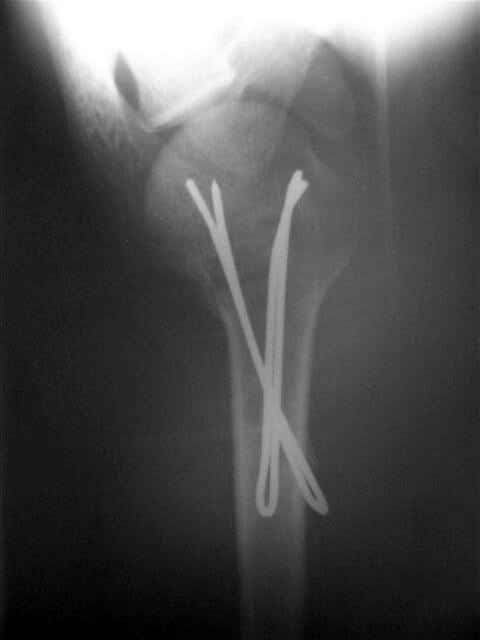

Посылаю послеоперационные Рг граммы.

Поздравляю, получилось просто замечательно. Если можно, расскажи чуть подробнее, как делали - как вправляли, как вводили спицы, поворачивали ли их?

Я и сам доволен результатом. В предпоследнем письме я кратко описал ход операции - закрыто репонировать не удалось( 2 недели с момента травмы и 1 неделя после неудачной репозиции) после удаления пучков спиц, пришлось сделать - 2см разрез на уровне перелома и с помощью периостального элеватора (золотое правило механики) *одеть* головку на дистальный отломок.

Спицы проводил через старые отверстия, вращая пучок импактором- направителем при его введении в головку.